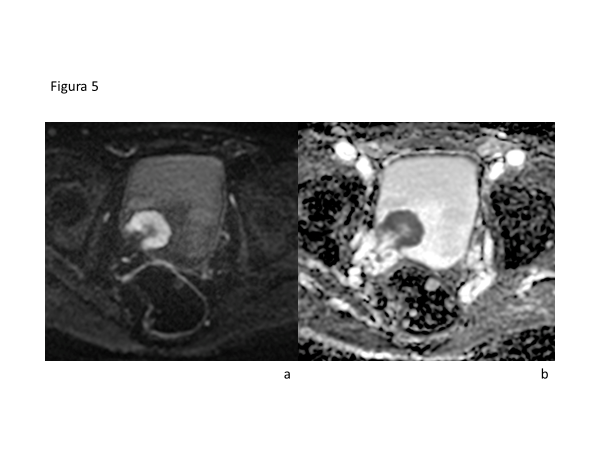

La RMmp de vejiga permite una adecuada estadificación local, ya que es capaz de diferenciar tumores invasores (que invaden músculo detrusor, por lo tanto estadío T2 o superior) de no invasores (T1 o inferior) e identificar la extensión a la grasa perivesical (T3) macroscópica y a órganos adyacentes (T4). Se ha reportado una exactitud de la RM con difusión y contraste intravenoso de hasta un 92% para diferenciar tumores T1 y T2 o mayores(31,32).

Los estudios se pueden realizar tanto en equipos de 1.5T o 3T, con bobina de pelvis de superficie (phased-array) y presencia de vejiga llena. El protocolo óptimo consta de secuencias morfológicas de alta resolución, con una gran capacidad de diferenciar la muscular de una lesión neoplásica como también de la grasa perivesical (secuencias T1 y T2) y secuencias funcionales de difusión y contraste intravenoso con gadolinio, que permiten evaluar el compromiso invasivo de la muscular.

El año 2018 fue desarrollado y publicado el Vesical Imaging-Reporting and Data System (VI-RADS), que busca estandarizar la adquisición y reporte de la Resonancia multiparamétrica (RMmp) de vejiga, definiendo el riesgo de invasión muscular, siendo aplicable a pacientes no tratados y a pacientes con resección transuretral diagnóstica. El sistema de puntuación aplicado va desde VI-RADS score 1 – 5, lo que se traduce en “altamente improbable invasión muscular” a “alta probabilidad de invasión muscular y extravesical” respectivamente. Usando este método se ha reportado un área bajo la curva ROC para invasión muscular de 0,94, con una sensibilidad de 87% y especificidad de 96% para VI-RADS 3 (invasión equivoca o con alta probabilidad)(32).

La utilización de la RMmp ofrece una oportunidad para reducir errores en la estadificación debido a una mejor visualización anatómica de la pared vesical además de ser un método con ausencia de radiación, lo que permite investigar en forma individual a pacientes en riesgo de CV, como también realizar estudio de imágenes previo, durante y en el seguimiento de respuesta a tratamiento (Figura 5).